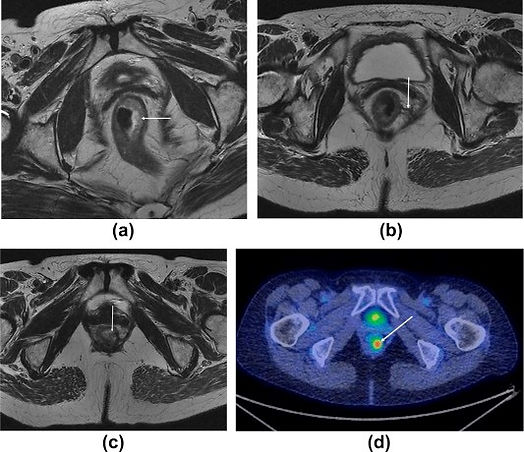

Görsel 1: Rektum tümörü ve incelenmesi.(a) Operasyon öncesi tümör T1.(b) TEM ameliyatı sonrası takip MR. (c) Endoskopik inceleme.(d) PET / CT inceleme.Transanal endoskopik mikrocerrahi, 1980’lerin başında Gehard Buess ve arkadaşları tarafından geliştirilerek cerrahların kullanımına sunuldu. İlk defa Almanya’da geliştirilen TEM, bugün tüm dünyada geleneksel transanal ve abdominal rektal rezeksiyon yöntemlerinin uygulanışına yeni bir yaklaşım imkânı sağlıyor. TEM günümüzde, minimal invaziv bir yöntem olmasıyla ve cerrahi açıdan sağladığı olanaklarla mortaliteyle daha fazla ilişkili olan “total mesorectal excision” (TME) yöntemine alternatif olmuş durumda. TEM yöntemi, 4 farklı parça içeren bir sistemin alanında uzman bir cerrah tarafından kullanımıyla lenf nodlarını eksize etmeden tümörün çıkarılması esasına dayanıyor. Tüm rektum kanseri vakalarında kullanımı uygun olmayan bu yöntem, vakaların TEM’e uygunluğunun seçimiyle başlıyor. Ameliyatta lezyon yerleşimine göre hastaya uygun pozisyon verilmesinin ardından ilk olarak rektum içine rectoscope yerleştirilip sonrasındaysa klasik yöntemlerle lezyon çıkarılıyor. Ameliyatta önce tümör tanımlanıyor ve tümör çevresinde yeterli miktarda bir rektal duvarın tam kalınlıkta kesimi yapılıyor. Cerrah, operasyon boyunca alanının 6 katı büyütme oranı ve 3 boyutlu bir görüntü sağlayan binoküler stereoskopik mercek yardımıyla işlemleri yürütüyor. Örnek rezeke ediliyor, ardından rektum duvarında oluşan defekt dikişlerle kapatılıyor. Bu dikişlerdeyse geleneksel laparoskopik dikiş yerine cerrahi klipsler ve metal boncukların kullanımı cerraha kolaylık sağlıyor. Bu yöntemin dezavantajlarına bakıldığında, lenf nodlarıyla yayılım gösteren kanserlere karşı yeterli etkinlik gösterememesi ve yüksek maliyeti uygulanımını azaltan etkenler olarak gözüküyor. TEM’e en uygun tip, T1 rektal kanserler olarak kabul edilse de seçilmiş T2 N0 rektal kanserler için de sonrasında TEM uygulanan neoadjuvan tedavinin onkolojik sonuçları ümit verici durumda ancak bu yaklaşım henüz değerlendirme aşamasında ve günümüzde klinik çalışmalarla sınırlı tutuluyor. TEM’in diğer kısıtlaması olan maliyeti de TEM platformunun özel alet ve masalarının satın alınmasının yanı sıra TEM insüflasyonu için gerekli olan tek kullanımlık ekipmanın sürekli değişim maliyetleri yüzünden ortaya çıkıyor. Yine de asıl maliyet ilk satın alımda gerçekleştiği için bu yöntemin kullanıldığı, çokça vaka gelen merkezlerde genel maliyetin TEM ile düştüğü görülüyor.